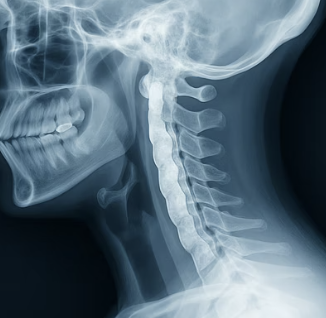

먼저 우리 목에 무슨 일이 일어나고 있는지부터 알아야 합니다. 우리 척추뼈 뒤쪽에는 뼈들을 안정적으로 연결해주는 '후종인대'라는 길고 튼튼한 띠가 있습니다. 그런데 알 수 없는 이유로 이 부드러워야 할 인대가 점점 뼈처럼 딱딱하게 변하면서 두꺼워지는 병이 바로 후종인대골화증입니다. 문제는 이 인대 바로 앞이 뇌에서부터 온몸으로 이어지는 신경 고속도로, 즉 '척수'가 지나가는 길이라는 점입니다.

인대가 뼈로 변해 두꺼워지면서 이 신경 고속도로를 점점 좁혀 들어오는 것이죠. 이미 좁아진 길을 더 이상 자극하지 않고, 안전하게 유지하는 것이 우리 일상생활의 가장 중요한 목표가 되어야 합니다. 이 원리를 이해하는 것이 모든 습관의 시작입니다.